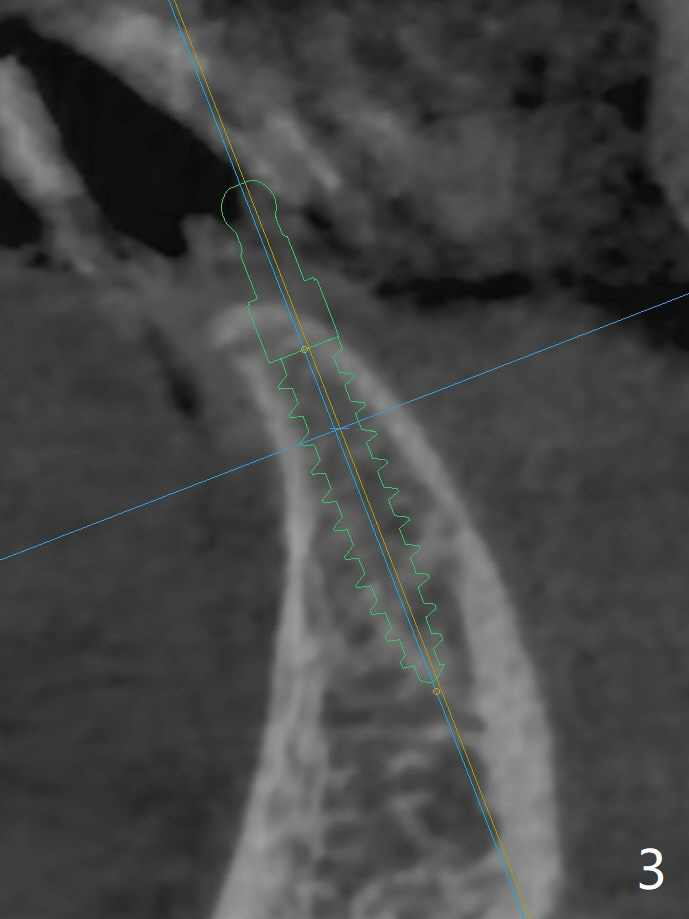

可以重做下颌7个连体牙冠,连接所有牙冠,中缝不再出现,但是费用高,口腔卫生不容易维持。简易办法是种植一个连体植体(1 -piece implant, 2.5x12(4) mm (直径,长度(袖),图二,图三(冠状截面))。 切口暴露狭窄牙槽嵴(图四),截除牙槽顶(图五黑色),然后在平坦骨面开始钻洞(图六红色箭头)。植体尽量种深点防止螺纹暴露,后期骨质密度容易增加。第一个钻头1.5x10毫米,拍摄根尖片,如果方位好,使用2x12mm, 2.5x6 mm钻头,或者2.5mm tap,植体植入。如果方位不好,纠正后,一定要有根尖片证实,才能用下一个钻头。牙槽嵴截除处骨质密度~700单位(图七),不是很高,放置植体前不必用同等大小钻头或者tap。